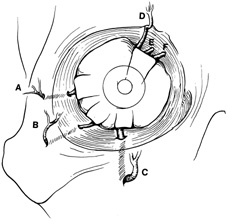

Once the outer surface of the lateral rim has been exposed, the periorbita along the mesial surface of the lateral wall is similarly elevated posteriorly within the orbit so that the bony lateral orbital rim can be completely bared along its external and internal surfaces. The periorbita is tightly adherent at the inner orbital rim (arcus marginalis), especially over the lateral orbital tubercle. Periorbital elevation in this area must be performed carefully to avoid buttonholing and prolapse of orbital fat. Once the elevation has proceeded along the inner surface posterior to the lateral orbital tubercle, the periorbita elevates quite freely from the bone. The zygomaticotemporal and zygomaticofacial neurovascular bundles are encountered about 1 cm posterior to the rim (Fig. 7). Transecting the neurovascular bundles results in a small area of postoperative hypesthesia over the lateral rim. These bundles usually are cut with a unipolar cautery to allow periorbital elevation to continue back to the inferior orbital fissure. The periorbita enters the inferior orbital fissure at the junction of the lateral wall and floor and is a landmark to establish the depth of dissection along the inner surface of the lateral rim.

Fig. 7. Coronal schematic view demonstrating major vessels penetrating periorbita and traversing the extraperiosteal space that may be encountered during periorbital elevation. (A, zygomaticotemporal artery; B, zygomaticofacial artery; C, communicating branch of infraorbital artery: D, supraorbital artery: E, posterior ethmoidal artery: F, anterior ethmoidal artery.)